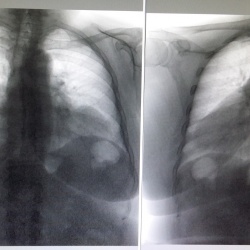

Коллеги нуждаюсь в вашей помощи, поступила тяжелая пациентка с признаками ТЭЛА, в очень тяжелом сосотоянии на ИВЛ. Д-димер более 4000, пытались законтрастировать, то что получилось видим ниже....